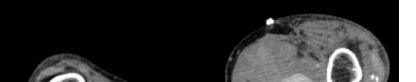

Her laboratory studies were notable for a hemoglobin of 11.9 grams per deciliter (g/dL) (reference range: 11.6-15 g/dL) and a normal white blood cell count of 8.4 thousand per cubic milliliter (k/μL) (reference range: 5-10 k/μL). Her lipase and liver function tests were within normal limits. Her human chorionic gonadotropin (hCG) had tripled from 6,253 milli-international units per milliliter (mIU/mL) (reference range: ≤2 mIU/mL) from her prior presentation to 18,038 mIU/mL. Transvaginal ultrasound showed a possible ectopic pregnancy adjacent to the right ovary and no intrauterine pregnancy (Image 1).

The patient declined medical abortion and was taken to the operating room for a right salpingectomy. On her initial presentation 11 days prior, the patient’s preoperative ultrasound had shown a complex focus of the left ovary with a hyperechoic thick rim suggestive of ectopic pregnancy and probable right-sided corpus luteal and anechoic cysts (Image 2, Image 3). No evidence of right ectopic pregnancy was documented intraoperatively during the patient’s initial salpingectomy. Pathology findings from the initial left- and subsequent right-sided procedures showed immature chorionic villi, congestion, and hemorrhage consistent with a tubal

Image 1. This image shows the patient’s ultrasound findings 11 days after her initial diagnosis of a left tubal pregnancy. The image on the left shows the right adnexa with an arrow pointing to a rounded cystic structure with a peripheral soft tissue component, blood flow, and free fluid. The image on the right shows the left ovary with two arrows pointing to a moderate amount of free fluid in the left adnexa. Image 2. This image shows the patient’s initial ultrasound findings. The image on the right shows two arrows pointing to the left adnexa with a complex focus measuring 2.5 x 2.6 x 2.6 centimeters (cm) with a cystic focus of 0.5 cm within it and a hyperechoic thick rim. The image on the left shows the right adnexa with arrows pointing to a small, probable 0.8 cm corpus luteal cyst and an anechoic cyst measuring 1.6 cm.

Image 3. This image shows both of the patient’s ultrasound findings as described above for ease of comparison. The upper panel is from the initial encounter and the lower panel is from the patient’s encounter 11 days later.